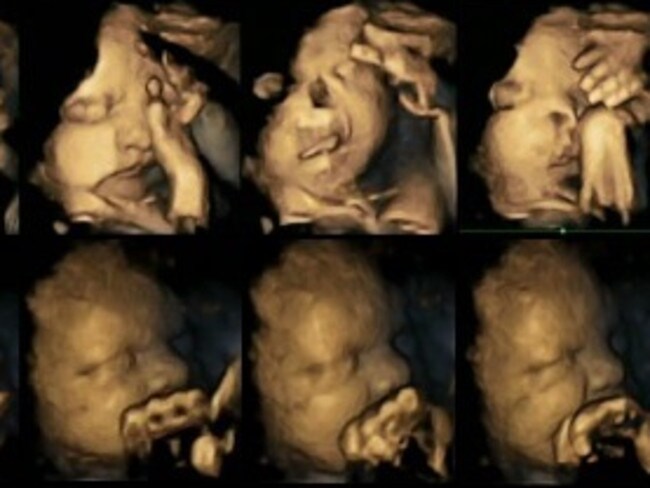

4D ultrasound study shows harmful effects of smoking on unborn babies From news.com.au

4D ultrasound study shows harmful effects of smoking on unborn babies Sometimes we are lucky enough to.